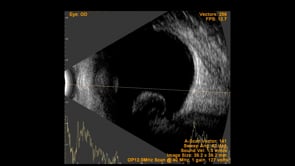

Left Eye B-scan ultrasound of a patient with old retinal detachment shows open funnel shaped hyperechoic membranous echoes, with high amplitude spikes on A-scan and a poor after-movement on dynamic B-scan, suggestive of retinal detachment. We can see a round echogenicity in sub-retinal location, with clear contents within, suggestive of a retinal cyst. This B-scan image is indicative of a long-standing chronic retinal detachment with secondary retinal cyst.

Photographer: Dr. Shraddha Raj Shrivastava

Condition/keywords: B scan ultrasound, chronic retinal detachment, OLD RD, open funnel RD, retinal cyst